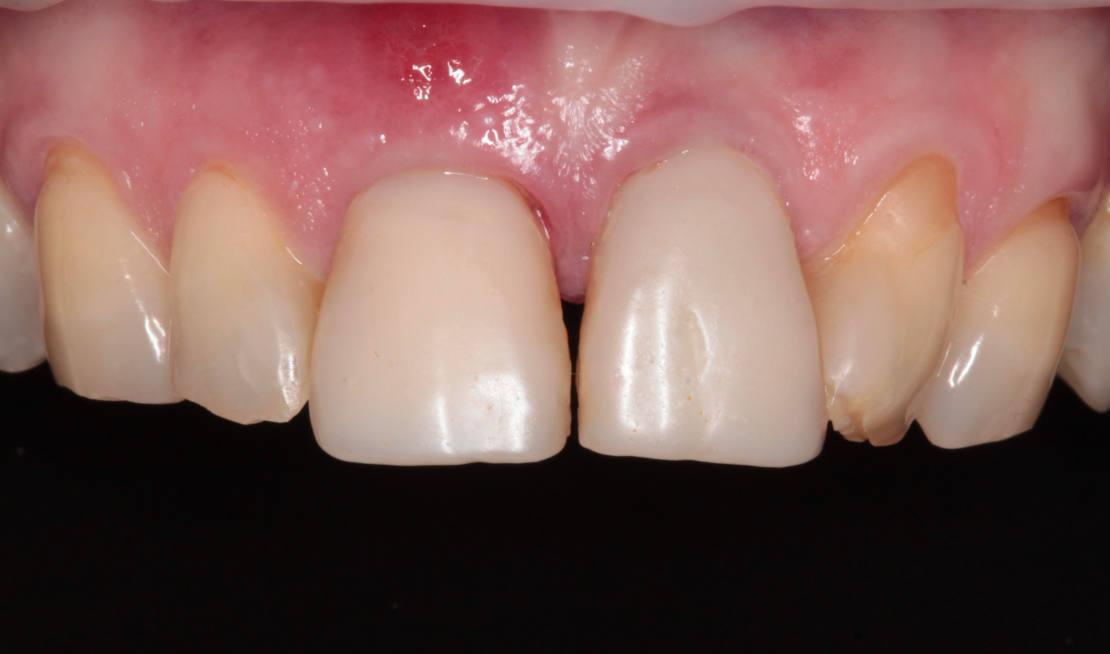

45-ročná pacientka sa obrátila na našu kliniku s bolesťou v oblasti horných stredných rezákov (obr. 1). Pri dôkladnom vyšetrení a CT diagnostike bola v oblasti zuba č. 11 zistená vertikálna fraktúra koreňa (obr. 2). V oblasti zuba č. 21 palatinálne bol prítomný hlboký kaz koreňa (obr. 3).

Vďaka týmto postupom bola operácia veľmi rýchla a pacientka odišla z ordinácie plne rehabilitovaná. Minimálne invazívnym spôsobom boli extrahované horné jednotky (obr. 6).

Kontrola po 10 dňoch (obr. 15–19).